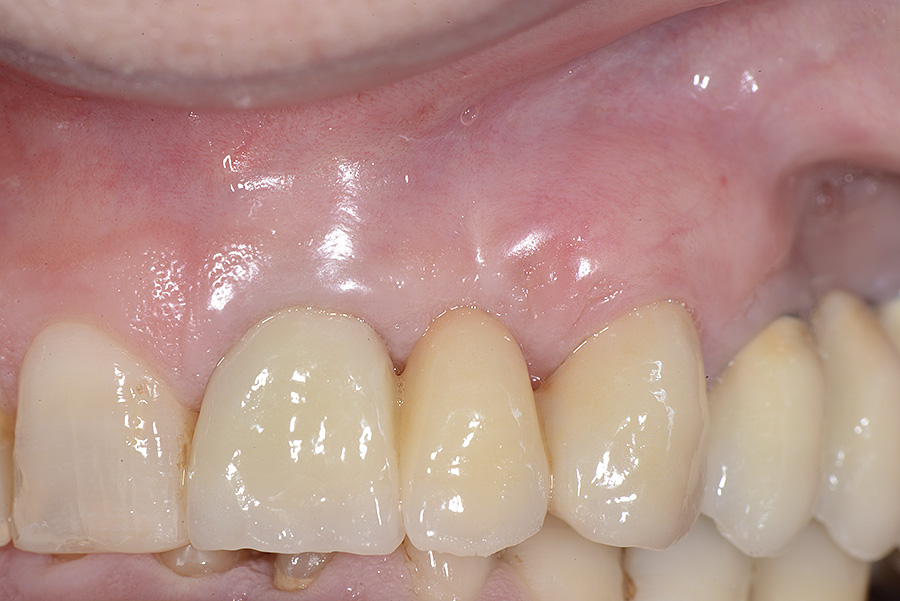

PREMESSA: in seguito all’estrazione dell’incisivo laterale superiore di destra, resasi necessaria per cause batteriche, si decide di affrontare il caso con il posizionamento di un impianto in sostituzione dell’elemento mancante dopo guarigione del sito infetto. Con tecniche rigenerative sia dei tessuti ossei mancanti a causa dell’infezione pregressa, sia dei tessuti gengivali che appaiono inizialmente troppo spostati in alto, si ripristina una corretta morfologia delle parabole (contorni) gengivali e delle papille interdentali (triangoli di gengiva tra due denti vicini).

Vengono utilizzati 2 tipi di provvisori: il primo, cementato ai denti vicini, viene utilizzato dal momento dell’estrazione del dente fino ad impianto osteointegrato (circa 6 mesi); il secondo, avvitato direttamente all’impianto, ha una funzione di prova estetica ma soprattutto di guida per la maturazione dei tessuti gengivali peri-implantari portandoli verso la maturazione completa prima di posizionare la corona finale in disilicato di litio.